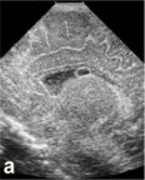

|  | | а - в проекции каудоталамической вырезки определяется кистозного характера включение, размерами 6х5мм, перекрывающее просвет бокового желудочка (перивентрикулярное кровоизлияние в стадии псевдокисты). | б - в проекции каудоталамической вырезки определяется кистозного характера многокамерное включение, размерами 14х6 мм, перекрывающее просвет бокового желудочка (перивентрикулярное кровоизлияние в стадии многокамерной псевдокисты), имеется фрагментация сосудистого сплетения. | |